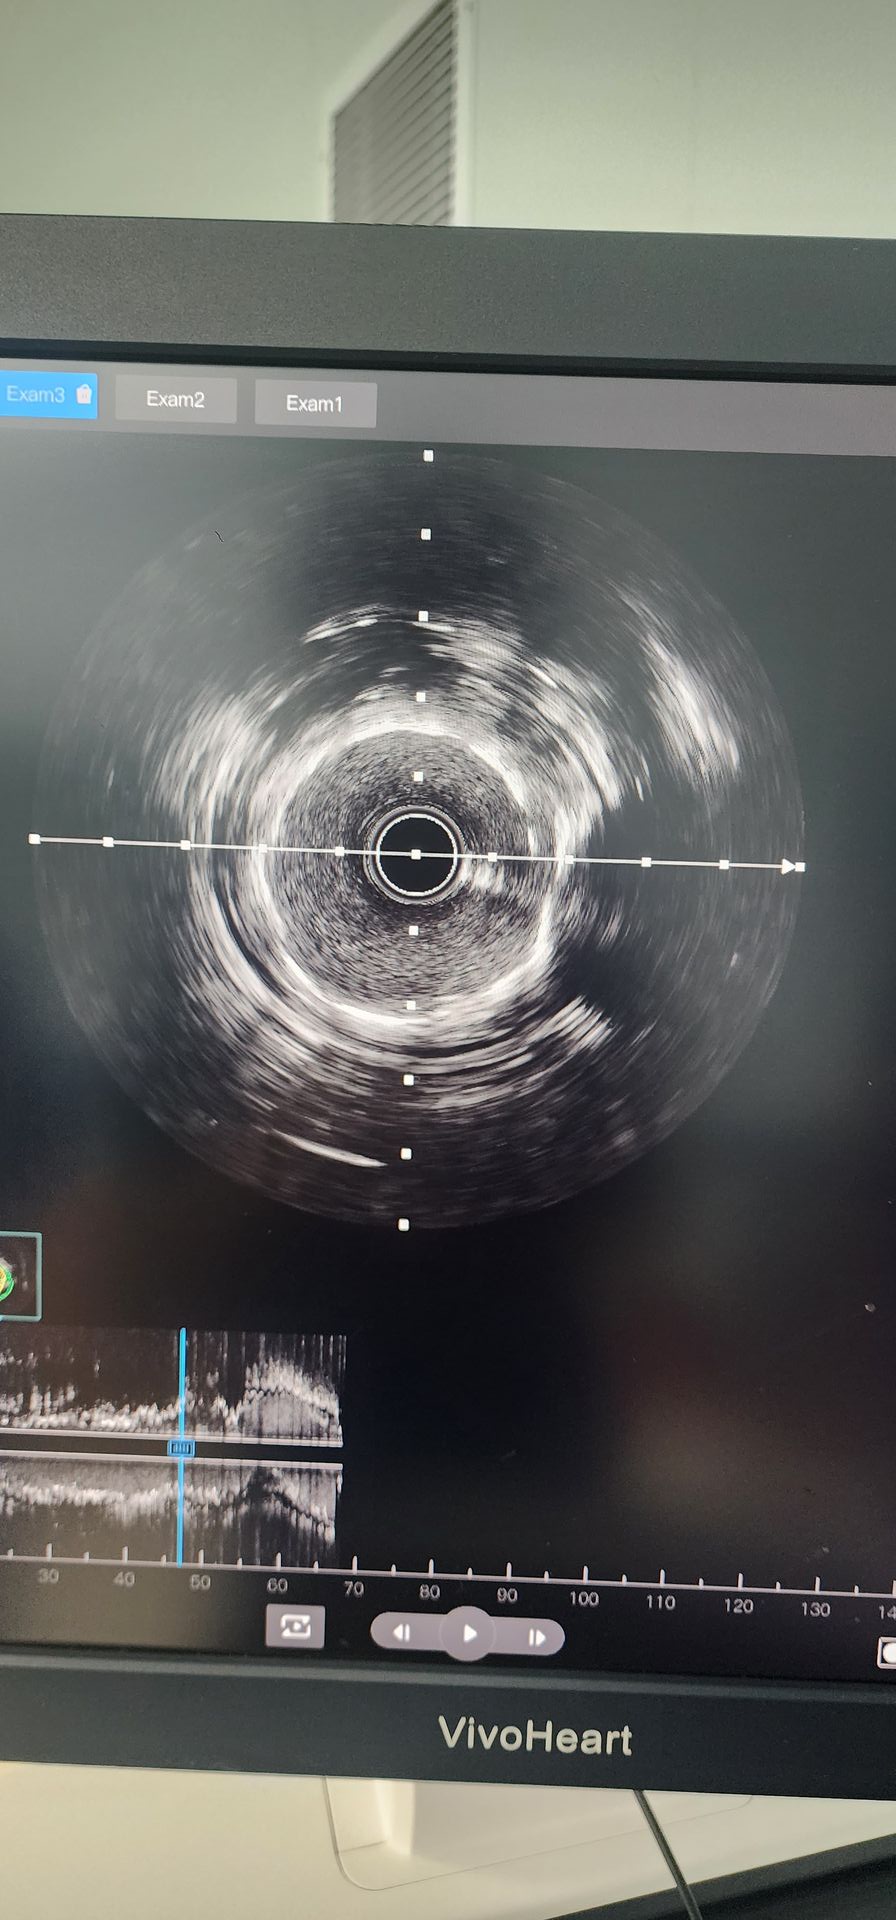

A angiografia coronária revelou calcificação grave com 95% de estenose na artéria circunflexa proximal e 85% a 90% de estenose calcificada na artéria coronária média direita.

Artéria circunflexa proximal: A pré-dilatação inicial com balão 2.0 × 20 apresentou resultados ruins. Foi então utilizado um cateter de dilatação coronária IVL balão 2,5 × 12 Lepu Vesscrack, realizando quatro ciclos, fraturando com sucesso a lesão calcificada. Após melhora significativa da estenose, um stent 2,5 × 14 foi implantado com sucesso, com resultados angiográficos satisfatórios.

Artéria coronária média direita: A pré-dilatação inicial com balão 2,5 × 20 resultou em melhora limitada. Um cateter de dilatação coronária IVL Lepu Vesscrack 2,5 × 12 foi então utilizado por dois ciclos, melhorando significativamente a estenose na lesão calcificada. Um stent 3,0 × 19 foi então implantado com sucesso, produzindo resultados angiográficos satisfatórios.